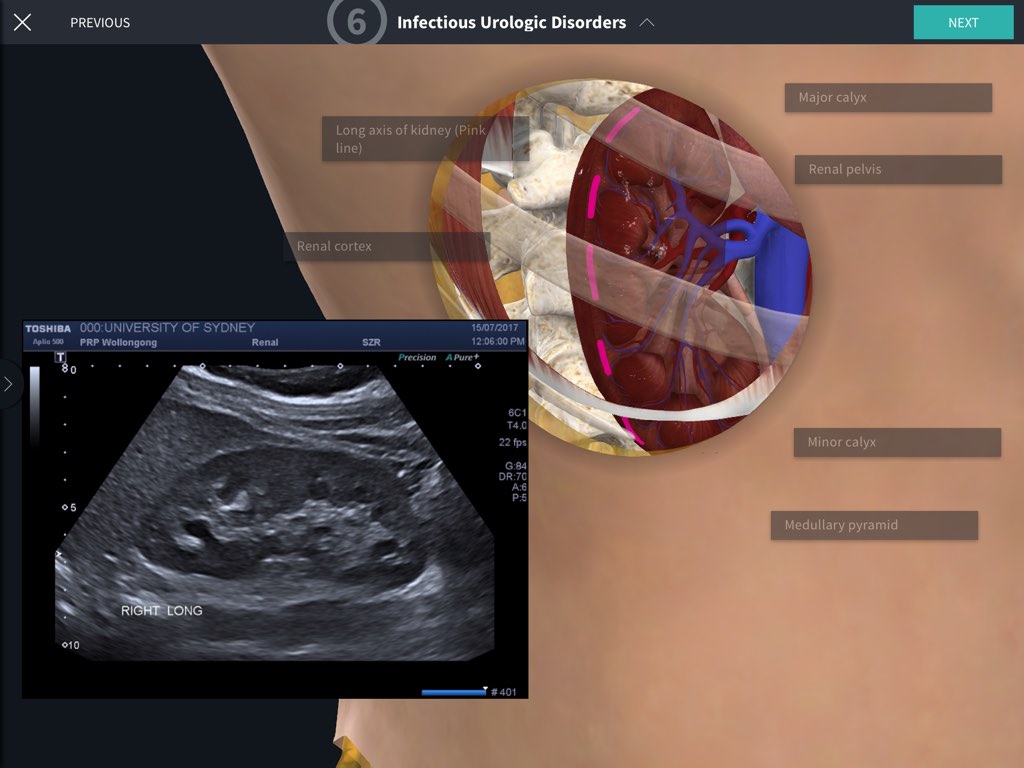

Point of Care Ultrasound